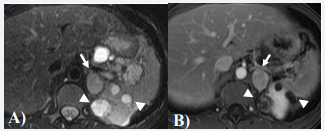

Both imaging features and laboratory values play an important role in the diagnosis of pheochromocytomas. While CT and MRI provide anatomic details, iodine - 131 metaiodobenzylguanidine (I131 - MIBG) scan gives functional assessment of pheochromocytomas. Elevation of urine and/ or blood catecholamine levels suggest active tumor. On CT, pheochromocytomas typically appear as solid or complex cystic adrenal masses with scattered areas of necrosis and hemorrhage, with possible calcifications [23]. On MRI, tumors are usually isointense or hypointense on T1-weighted images, and hyperintense on T2- weighted images with marked enhancement during the arterial phase of dynamic study after contrast administration (Figure 6) [26].

Pheochromocytoma in a 30-year-old woman with known von Hippel Lindau Disease. Axial T2 weighted (A) and contrast enhanced T1 weighted (B) images show a well- circumscribed T2- hyperintense focal lesion in the left adrenal gland, which enhances after contrast adminstration (arrow). In addition, also note mutiple cystic masses in the left kidney (arrowheads).

Figure 6: Pheochromocytoma in a 30-year-old woman with known von Hippel Lindau Disease. Axial T2 weighted (A) and contrast enhanced T1 weighted (B) images show a well- circumscribed T2- hyperintense focal lesion in the left adrenal gland, which enhances after contrast adminstration (arrow). In addition, also note mutiple cystic masses in the left kidney (arrowheads).

I-131 MIBG scan shows high uptake in 75–95% of cases and is used to localize and identify pheochromocytoma and paraganglioma, especially when the presence of more than one tumor is suspected. The treatment of choice is complete surgical resection with pre-operative pharmacological control of hypertension; tumor size greater than 3.5 cm, increased MIBG uptake, and abnormal function are indications for surgery [1]. The screening protocol includes monitoring of annual plasma or 24-hour urinary catecholamine levels from the age of 2 years along with annual blood pressure measurement [1]. No imaging is deemed necessary until catecholamine levels are increased on follow up.